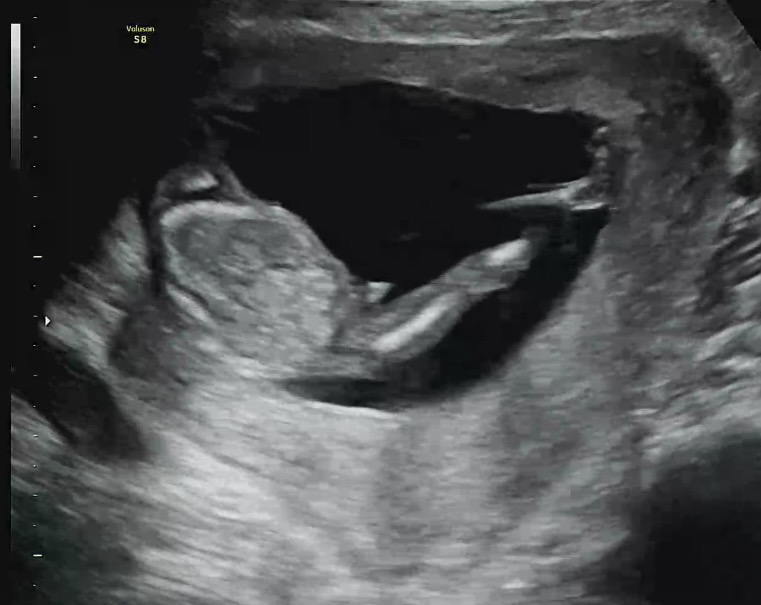

14주 초음파 각도법 질문드려용🥹

뭐가 보인다고 하셨는데 다리 쭉 뻗었을 때 저 각도면 아들이 확실하겠죠,,? 다들 어떻게 보이시나용😹